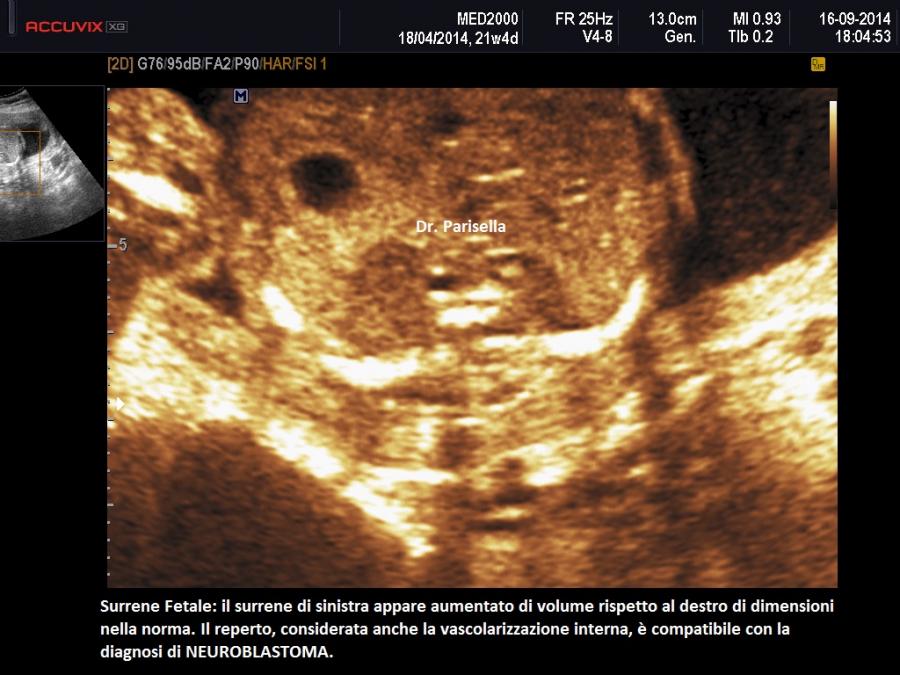

In presenza di una massa del surrene il primo sospetto deve essere orientato verso il neuroblastoma che rappresenta il tumore solido più frequente in età infantile, con una incidenza di circa 1:7000 - 1:10000.  Il tumore può presentarsi come una neoformazione monolaterale o bilaterale, in forma cistica, solida o complessa, riccamente vascolarizzata al Color-Doppler. Può metastatizzare il fegato, provocando epatomegalia, e la placenta provocando placentomegalia; altro segno legato alla metastatizzazione è l'idrope.

Dal punto di vista prognostico vi è una notevole discrepanza tra le forme diagnosticate in utero e quelle ad insorgenza postnatale. Le prime hanno in genere una prognosi favorevole con regressione spontanea della lesione in circa il 40% dei casi.  Le seconde hanno prognosi infausta.